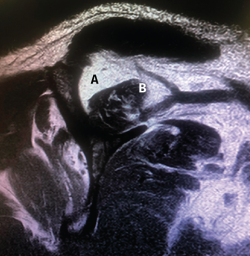

Figura 1. Rotura en forma creciente. A: acromion; B: rotura en forma de semiluna del tendón supraespinoso.

Figura 5. Rotura de tipo C1. A: rotura pequeña de espesor completo del supraespinoso; B: cabeza humeral.

Sin embargo, las clasificaciones basadas en el tamaño de la rotura deben ser bidimensionales, ya que la visión unidimensional puede ser engañosa, al mostrar el tamaño de la rotura solo desde el plano anteroposterior(4). Por esta razón, proponemos el sistema de clasificación del manguito posterosuperior sugerida por Snyder, que aporta información no solo del tamaño, sino del número de tendones afectados y la presencia de tejido cicatricial(7). En las lesiones de tipo C1 la lesión atraviesa todo el espesor del tendón y en el eje transversal es pequeña y punzante (Figura 5). Las de tipo C2 son roturas de espesor completo pero la distancia entre los extremos de la rotura es menor de 2 cm con escasa retracción (Figura 6). En las de tipo C3 la rotura afecta en sentido transversal entre 3 y 4 cm con mayor retracción implicando 2 tendones (Figura 7). Y las de tipo C4 son la rotura masiva del manguito de los rotadores con una afectación de espesor completo de toda la anchura de 2 o más tendones asociando importante retracción (Figura 8).